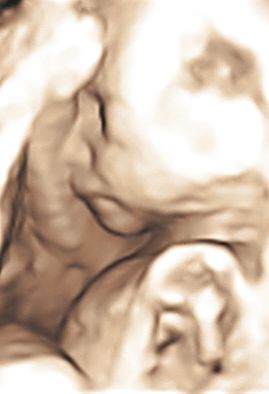

Я со своим ходила, если не ошибаюсь в 31 или 32 недели - раньше не получалось, было все так здорово видно, правда сынок спал и сосал пальчик на ножке) вот фото

по-моему где-то 31-32 недели, помню нам в одной клинике отказали делать 3Д, сказали, что после 29 недель уже ребеночек большой и будет плохо видно, но как оказалось-все было отлично видно и интересно)))